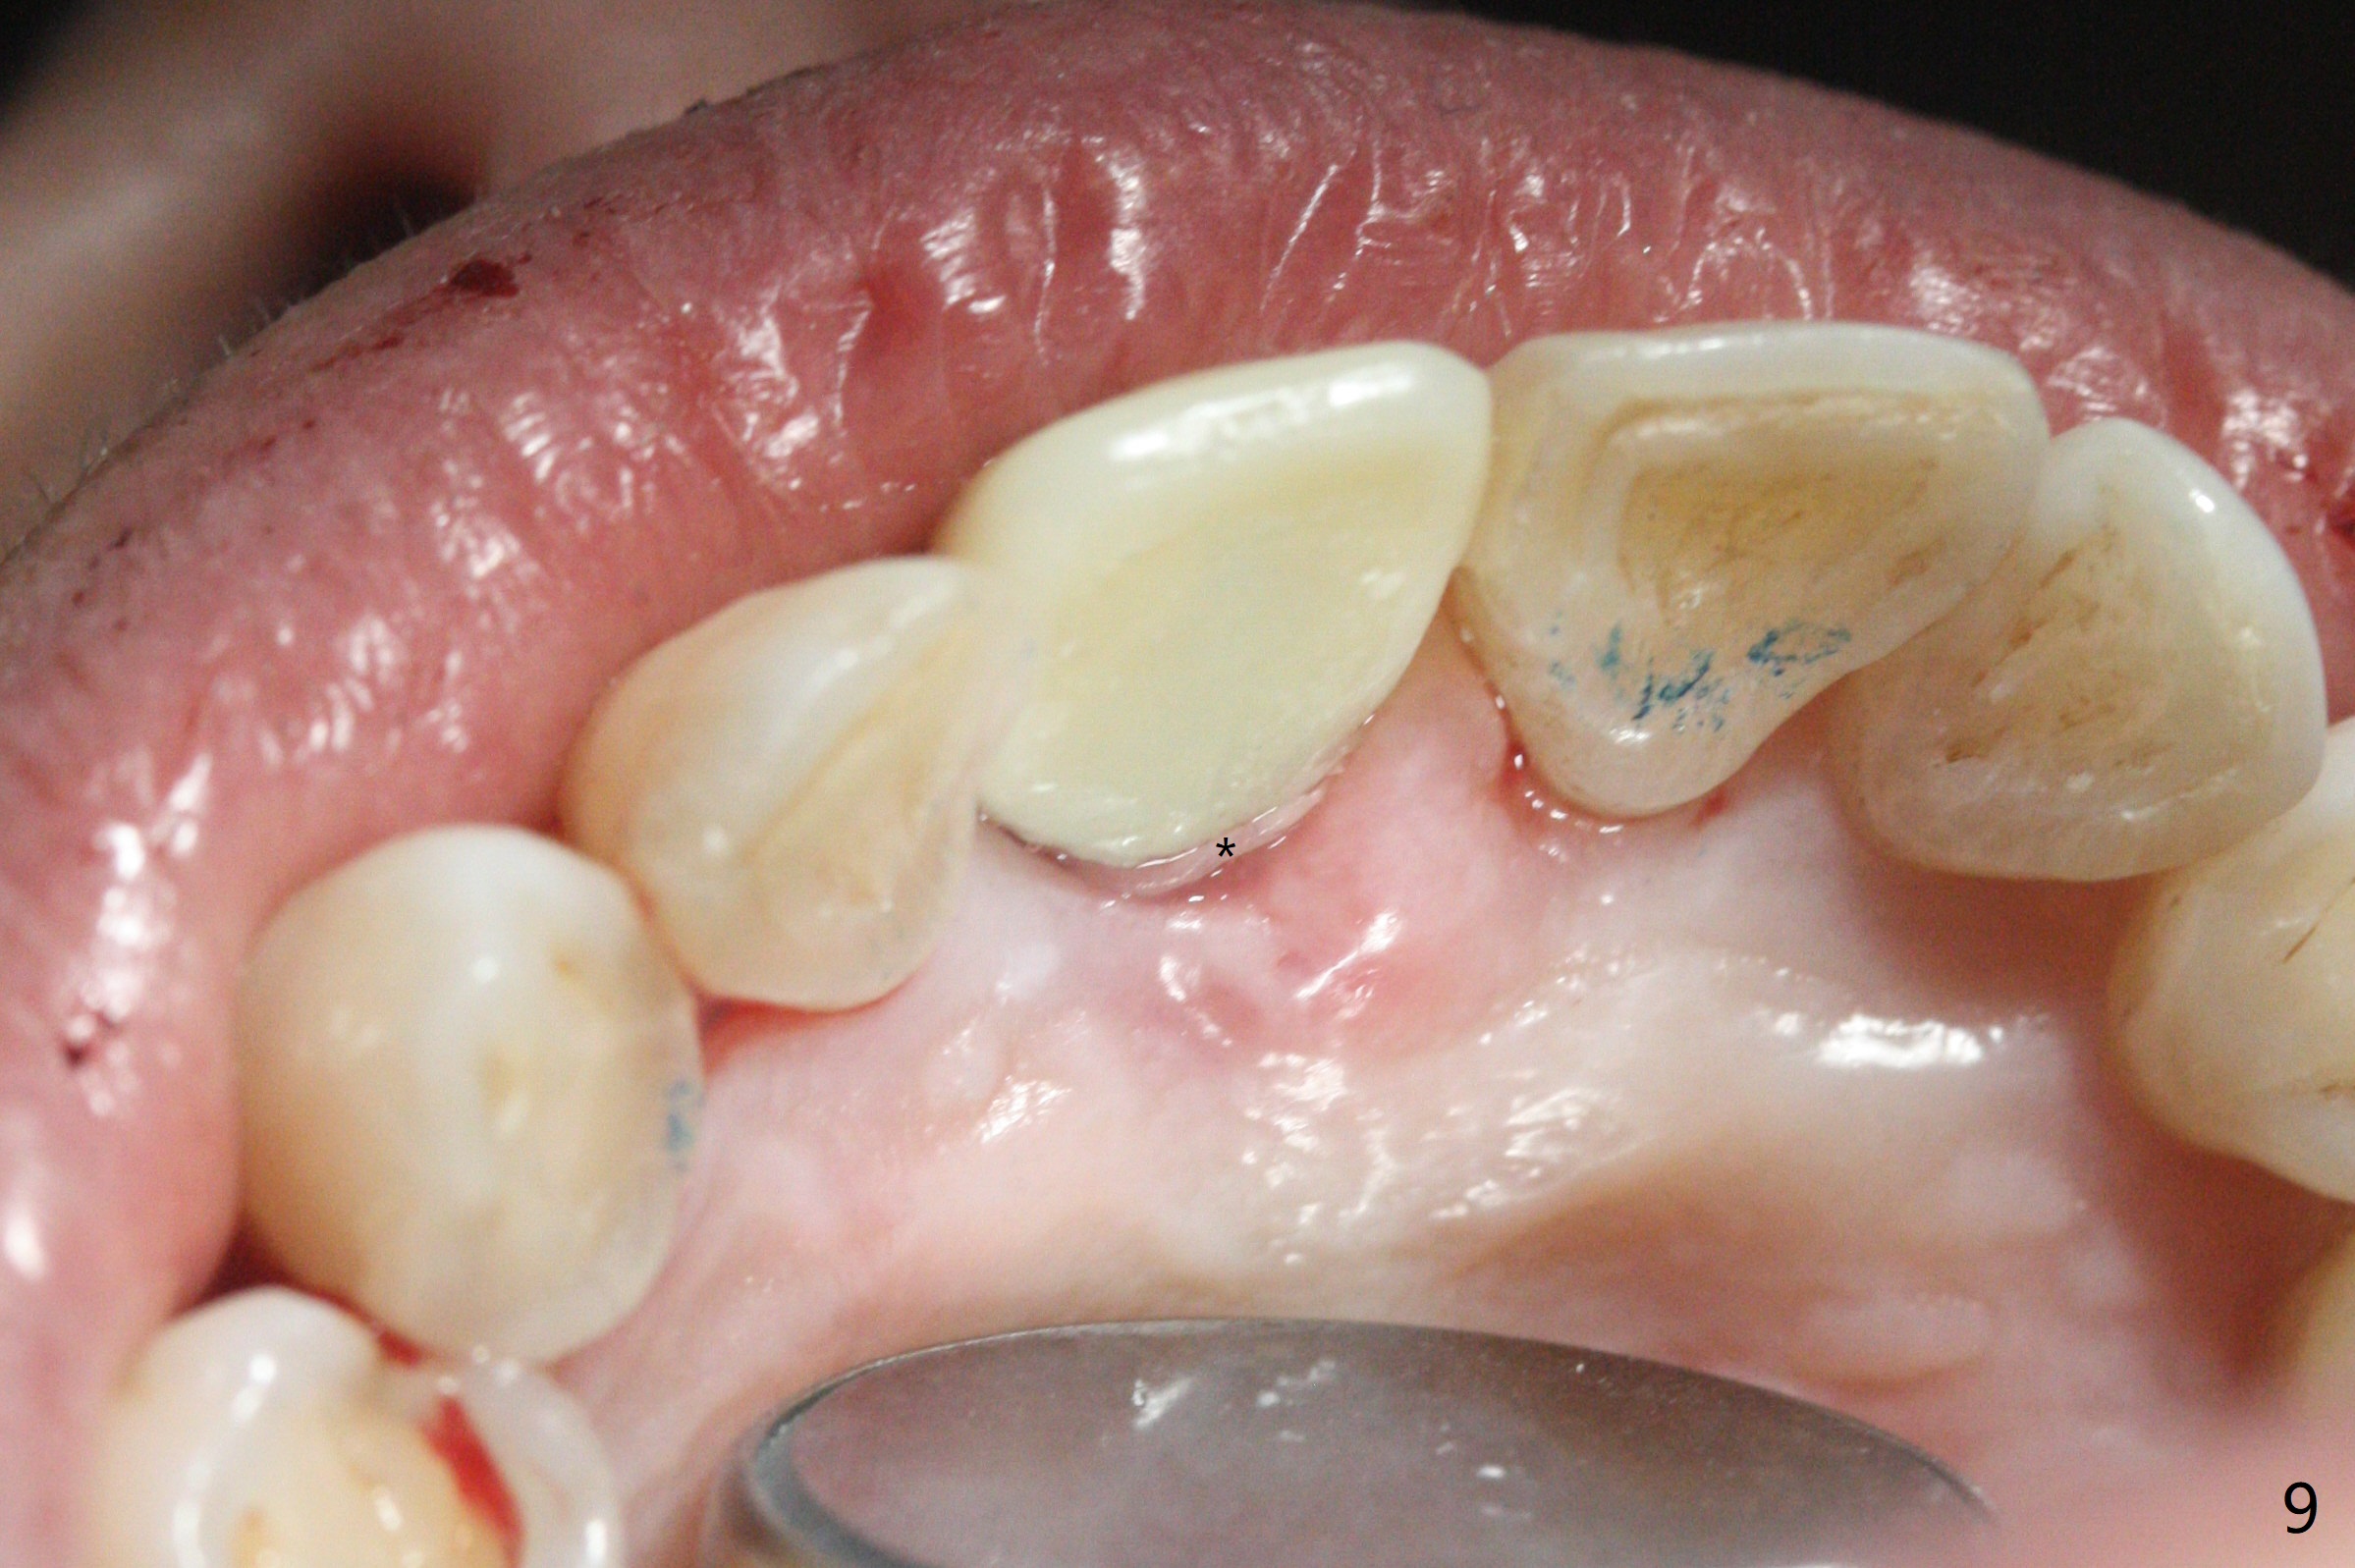

59岁女术前右下1,2切缘磨短后,右上1颊侧移位得到纠正(图一(咬合创伤))。拔牙后证实颊侧骨板缺失,钻洞始于腭侧(图二),当1.5毫米钻头感觉刚穿破鼻底时,置入2.5x14(4)毫米一段式植体,好像进入鼻腔,但是扭力<10Ncm(图三)。把一张PRF膜放入牙槽窝,一端紧贴颊侧牙龈腭侧,另一端放置颊侧牙龈颊侧(图四),然后开始用粘性骨粉(图五,七:*(100%皮质骨))充填颊侧间隙。后者填满时(图五:*),将外面一端PRF翻转覆盖牙槽窝开口,并插入基台固定(图六),最后插入龈下,用临时牙冠固定(图八(T),九(*:PRF))。术后九天牙龈退缩(图十:^),临时牙冠突出(*),后者龈缘和切缘进行调整,缩短(图十一,十二),少许骨粉暴露(图十二:>),十四天后牙龈往下生长,好像形成角化龈(图十三:*)。